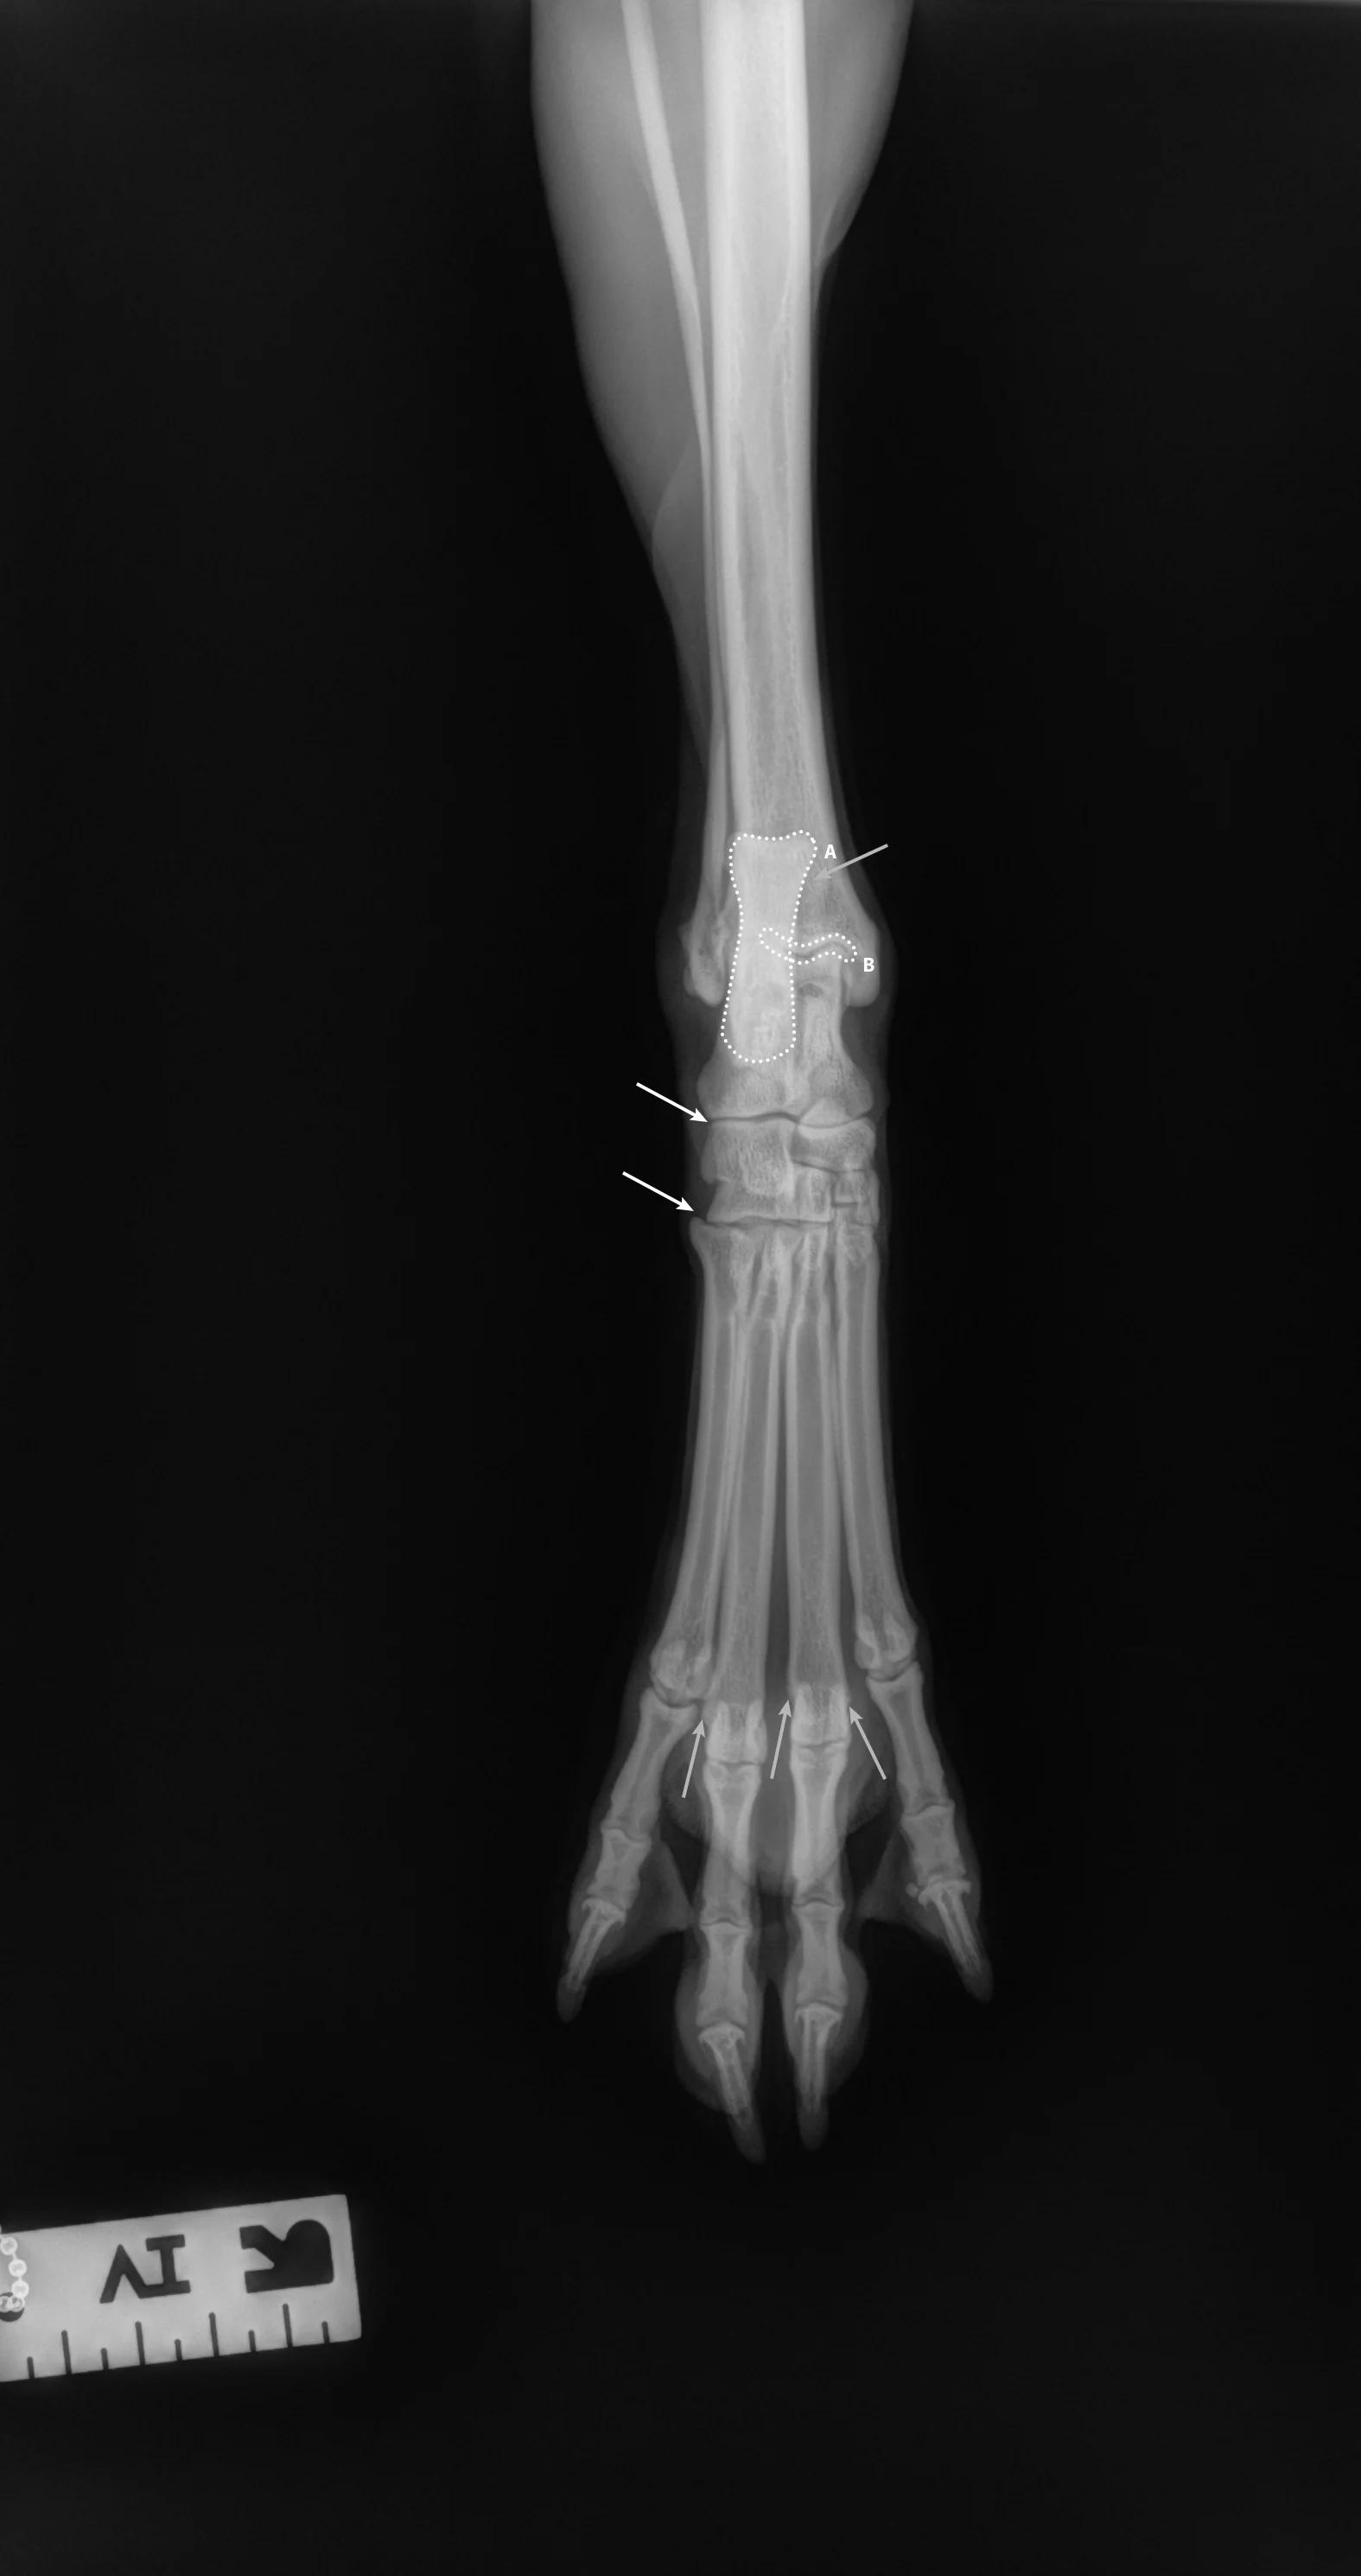

Step-by-Step: Positioning a Pelvic Limb for a Dorsal/Palmar View of the Digits

Step 1: Position the Patient

Place the patient in dorsal recumbency. Center the abdomen over a V-trough sponge positioner to keep the body straight; ensure the pelvis and caudal abdomen are outside of the trough. Make sure both pelvic limbs are completely extended and the unaffected limb is not in the imaging view.

Author Insight

To evaluate the entire bony structures, the digits may need to be separated manually (using either a wooden spoon to press down and spread the digits or using gauze without woven radiopaque detectors) and taped down.

Step 2: Position the Beam

Center the collimator beam over the tarsometatarsal joints to include the distal metatarsals and all digits (the tarsus can also be included).

All digits should be separated and clearly visible. The bony edges of the metacarpal bones should be parallel to each other (arrows), and all phalanges (P1 [A], P2 [B], P3 and nail [C]) should be included.